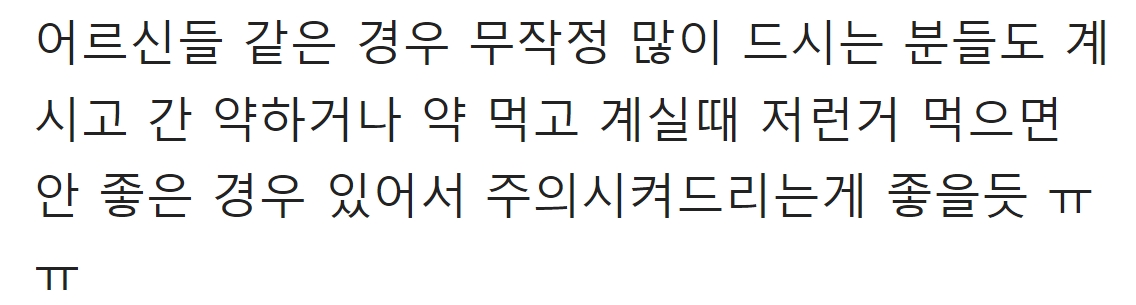

해당 게시물에는 먹으면 오히려 몸에 안좋은 영양제들이 올라왔다.

해당 게시물을 접한 누리꾼들은 “와 반전이네…먹고 있었는데”, “전혀 몰랐네…”,”몸에 좋다고 선물 받았는데 아니네ㅠㅠ” 라며 현재 다양한 반응을 보이고 있다.